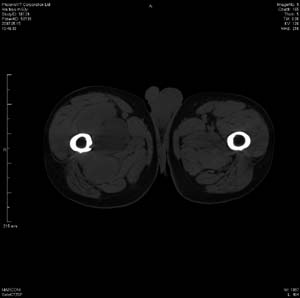

男 63岁 右大腿无痛性肿块11年,x片右大腿软组织肿块影,余无明显异常.ct值-13__239hu

右大腿股内侧股与收肌间隙间多发囊实性占位,界清.内示斑点状钙化.局部骨质无异常.肌肉推压移位表现.

考虑肌间隙病变.可有1,神经来源肿瘤.2,血管来源病变.3,淋巴来源肿瘤.4,脂肪来源肿瘤.5,滑膜来源肿瘤.结合病史只能考虑良性占位.建议增强或mri进一步分析.

同意,病史较长,病变周围分界清晰,考虑良性病变。病灶内有多发斑点状钙化,沿肌间隙生长,血管瘤或淋巴管瘤首先考虑。